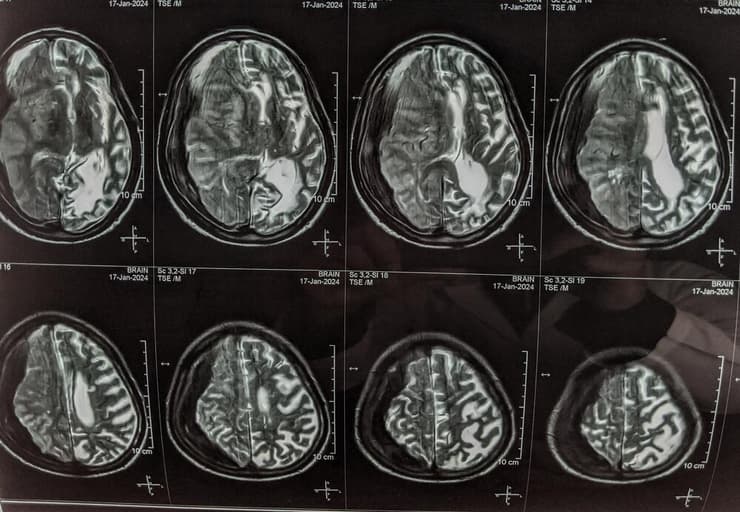

פריצת דרך ישראלית בתחום השיקום המוחי: מערכת טיפולית ראשונה מסוגה בעולם לשימוש ביתי אוטונומי, המבוססת על בינה מלאכותית ושדה אלקטרומגנטי מותאם אישית, הראתה תוצאות מבטיחות בטיפול בנפגעי שבץ מוחי. במחקר חדש שפורסם לאחרונה בכתב העת JAMA Network Open, הצליחה המערכת החדשה, פרי פיתוחה של חברת BRAIN.Q הישראלית, שאושרה לאחרונה לשימוש בישראל ובאירופה, להפחית משמעותית את דרגת הנכות גם כאשר הטיפול החל שבועות וחודשים לאחר האירוע המוחי - חלון זמנים שבו עד כה לא היה בנמצא טיפול יעיל.

כדי להבין את גודל החידוש, צריך להבין איך פועל המוח וכיצד הטכנולוגיה יכולה ללמד אותו להשתקם. "בן אדם אחרי שבץ מוחי משותק בחצי גוף. הבעיה היא לא ביד או ברגל, אלא במוח", מסביר דרקסלר. "הסיבה שהוא משותק היא כי אזורים שונים ברשתות שהיו קשורות לאותה פגיעה מוטורית נפגעו. איך אני משקם? אני מעודד את הרשת למצוא את המעקף לאזור הפגוע ולמצוא את הדרך להתחווט ולהתארגן מחדש".

המערכת, הוא מסביר, משתמשת באלגוריתם של בינה מלאכותית שמאפיין את החתימות של הרשתות הפגועות, השומר על שדה אלקטרומגנטי המותאם אישית לעידוד חיווט מחדש שלהן. "האלגוריתם מנתח את החתימות של רשתות שנפגעו במוח: ולאחר מכן מייצג שדה אלקטרומגנטי מותאם בפרמטרים שלו, בצירוף של תוכנית תרגילים מסונכרנת.